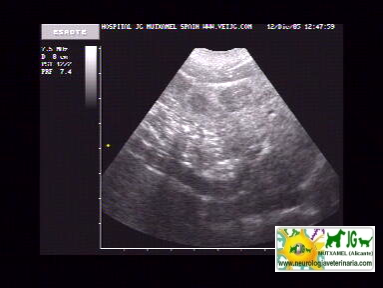

Se aprecia la vena porta muy aumentada de tamaño y sinuosa, por lo que es previsible que haya shunts, aunque no los distingamos |

video de ecografía sin doppler: |